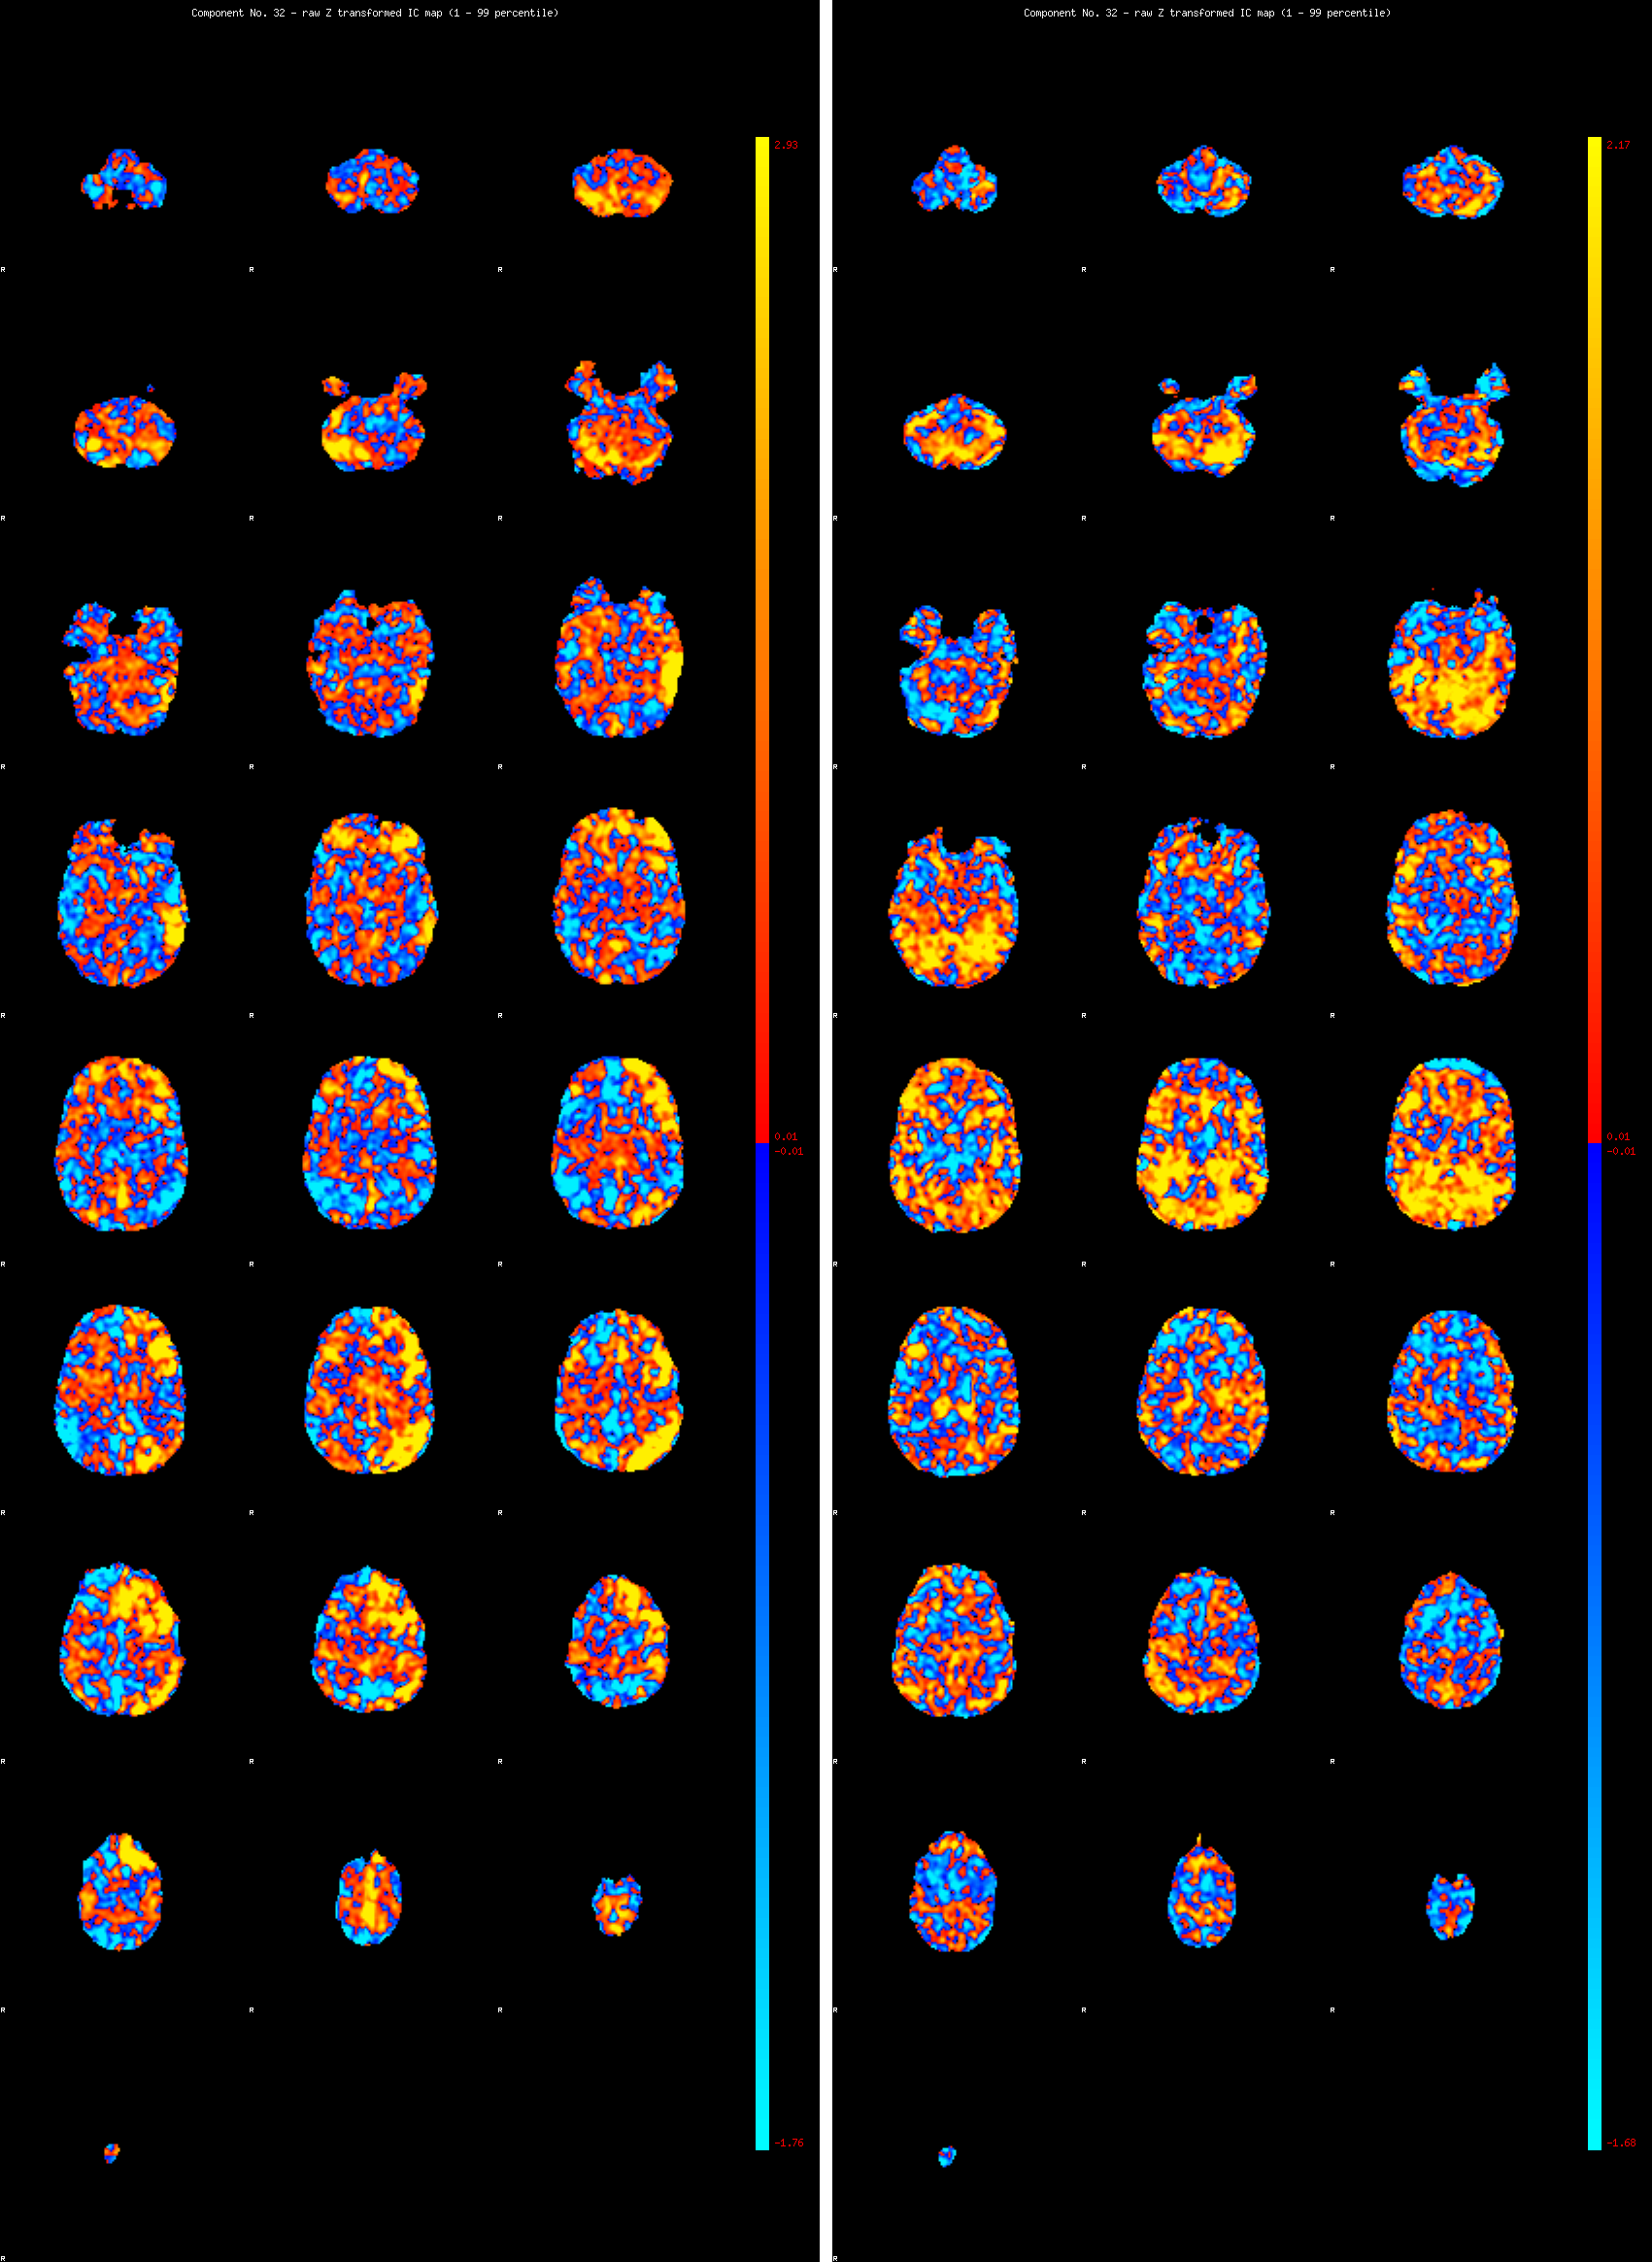

Pour la station 3, le container présente une documentation sur Matt Mullican : des images des IRM qu’il a réalisées à Londres, certaines quand il était sous hypnose, d’autres en état normal.

Investissant à la fois les champs de la performance, de l’installation, de l’outil numérique ou de la sculpture, Matt Mullican travaille à l’élaboration d’un modèle de cosmologie constitué par un vocabulaire formel et symbolique personnel. L’hypnose et la cartographie sont les principaux modes opératoires de son œuvre.